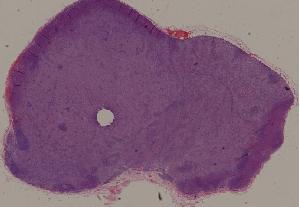

90.皮肤瘤型麻风